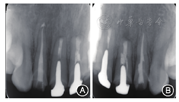

根尖X线片 A:

根尖病变明显缩小;B:

根尖病变明显缩小

根尖病变愈合;B:

根尖病变接近愈合

叩诊正常,不松动,牙龈色泽正常,切口位置可见隐约瘢痕。根尖X线片显示

根尖无明显病变。

根尖无明显病变;B:

根尖无明显病变